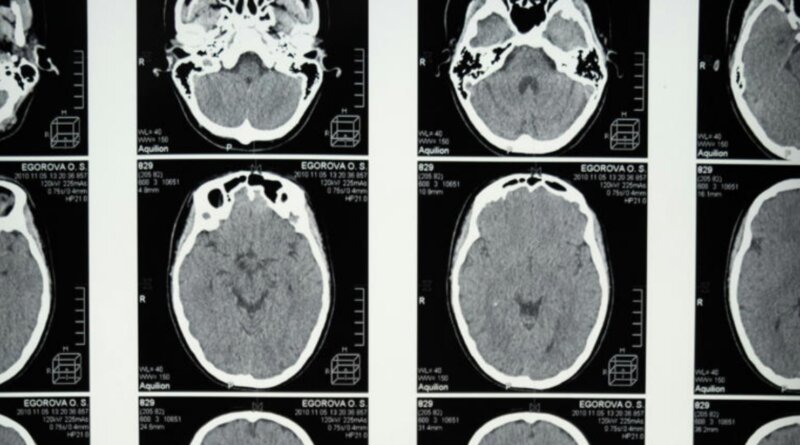

Inyectan US$ 106 millones en una nueva apuesta neurológica: buscan revolucionar el tratamiento del tinnitus, la esquizofrenia y la epilepsia

La carrera por desarrollar nuevos tratamientos neurológicos acaba de sumar un jugador que ya está dando de qué hablar. Una